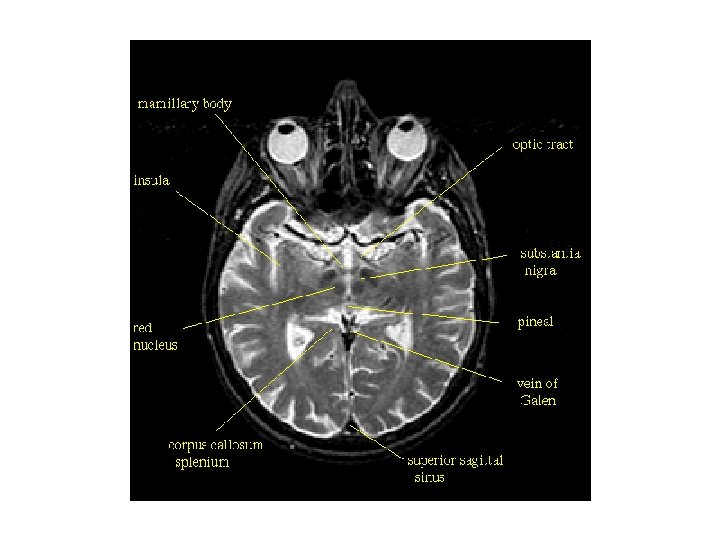

1. 송과체(pineal body) 2. 상구(superior colliculus) 3. 하구(inferior colliculus) 4. 하구완(brachium of inferior colliculus) 5. 대뇌각(cerebral peduncle) 6. 소뇌반구(cerebellar hemisphere) 7. 소뇌벌레(cerebellar vermis) 8. 교뇌(pons) 9. 제 4뇌실(4 th ventricle) 10. 빗장(obex) 11. 수뇌(myelencephalon) 12. 척수(spinal cord) Ⅴ. 삼차신경(trigeminal nerve) Ⅶ. 안면신경(facial nerve) Ⅷ. 전정달팽이신경(vestibulocochlear nerve)

대뇌 내측표면에서 관찰되는 구조 1. 내측전두이랑(medial frontal gyrus) 3. 대상고랑(cingulate sulcus, 대상구) 5. 중심옆고랑(paracentral sulcus) 7. 대상고랑 변연부(marginal portion) 9. 두정후두고랑(parieto-occipital sulcus) 11. 새발톱고랑(calcarine sulcus, 조거구) 13. 송과체(pineal body) 15. 제 4뇌실(4 th ventricle) 17. 시상간접합부(interthalamic adhesion, 시상간교) 19. 시각신경(optic nerve, 시신경) 21. 뇌량하구역(subcallosal area) 2. 대상이랑(cingulate gyrus, 대상회) 4. 뇌량(corpus callosum) 6. 중심옆소엽(paracentral lobule) 8. 쐐기앞소엽(precuneus, 설전부) 10. 쐐기부분(cuneus, 설부) 12. 혀이랑(lingual gyrus, 설상회) 14. 중뇌수도관(cerebral aqueduct) 16. 시상(thalamus) 18. 뇌하수체(pituitary gland) 20. 후각망울(olfactory bulb, 후각구) 22. 종팔판옆이랑(paraterminal gyrus, 종판방회)